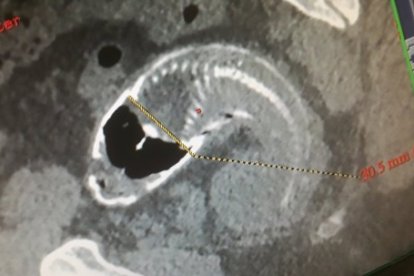

Ya en la casa de salud, lo sometieron a una serie de tomografías computarizadas y rayos X que revelaron una tilapia de Mozambique, un pez de agua dulce, dentro de su humanidad.

Al principio, los médicos trataron de extraer el pescado a través de una endoscopia de emergencia, pero descubrieron que la tilapia era demasiado grande.

Luego de varios intentos fallidos, los cirujanos decidieron abrir su abdomen después de descubrir que las aletas espinosas del animal habían causado rupturas en su intestino grueso.